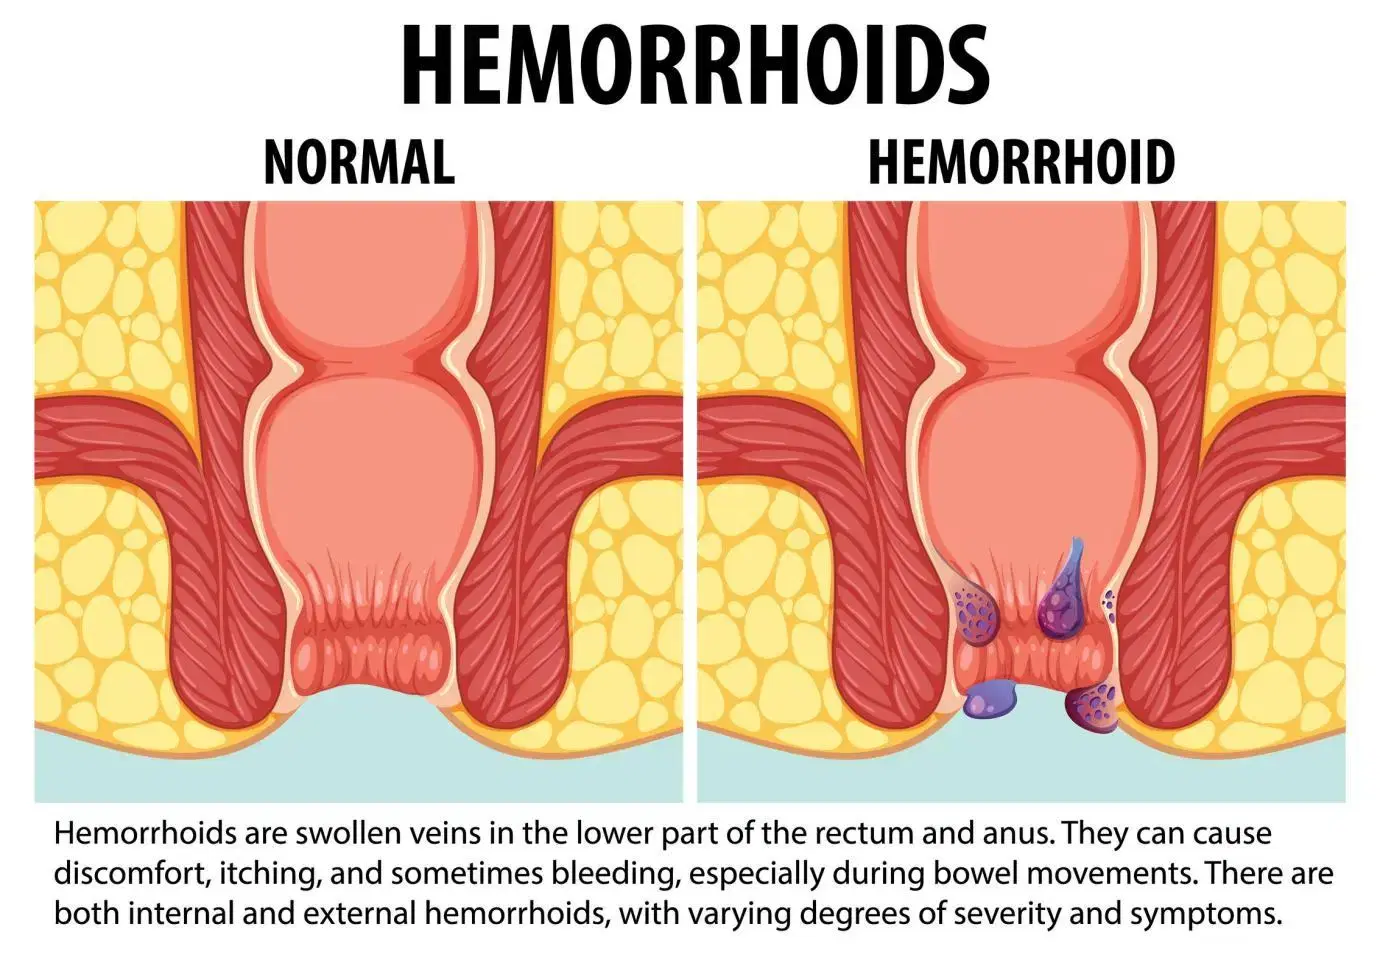

Piles Treatment in Vijayawada

At Vijayawada Gastro Centre, we provide advanced and minimally invasive treatment for piles, offering personalized care for fast and effective relief. Piles are swollen veins in the anal or rectal region, causing pain, bleeding, itching, and discomfort. Our experts use modern diagnostic tools such as anoscopy and colonoscopy to ensure accurate evaluation. Treatment options include lifestyle changes, medications, rubber band ligation, sclerotherapy, infrared coagulation, and advanced laser therapy. Laser treatment offers minimal pain, quick recovery, and same-day discharge. Our specialists ensure compassionate, safe, and tailored care for every patient.